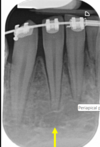

1

Not at all